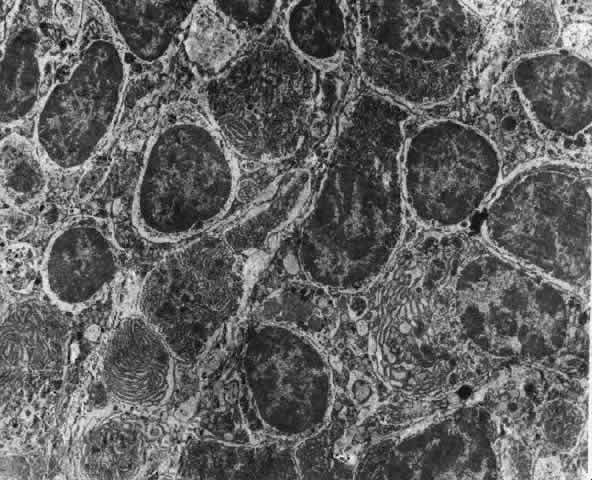

Fig. 22. Electron micrograph of an area of active scleritis showing the plasma cell

infiltrate suggestive of an immune response. Note aggregated plasma

cells, with the characteristic whorled rough endoplasmic reticulum, in

the process of degeneration, releasing organelles and nuclear debris

into the extracellular matrix. (Uranyl acetate and lead citrate. X3000) (Courtesy of Dr. R. Tripathi) Fig. 22. Electron micrograph of an area of active scleritis showing the plasma cell

infiltrate suggestive of an immune response. Note aggregated plasma

cells, with the characteristic whorled rough endoplasmic reticulum, in

the process of degeneration, releasing organelles and nuclear debris

into the extracellular matrix. (Uranyl acetate and lead citrate. X3000) (Courtesy of Dr. R. Tripathi)

|